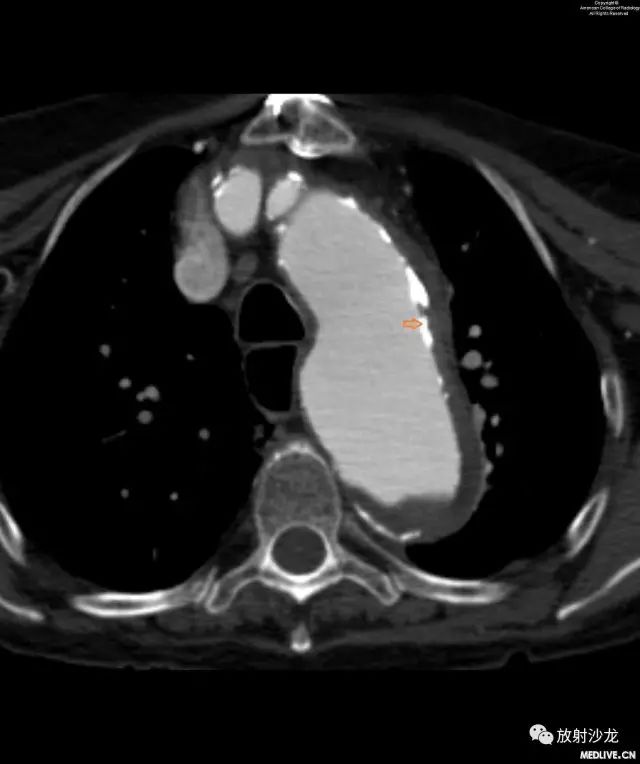

图3和图4:CT平扫和增强扫描显示由于壁内血肿(intramural hematoma,IMH)而移位的主动脉钙化。注意IMH呈稍高密度影,这提示出血是急性的。